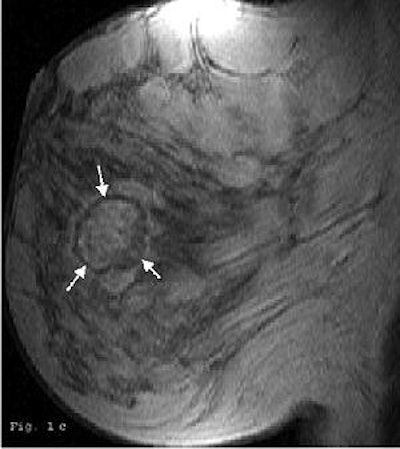

| Forty-five-year-old woman with 3-cm clinical lesion in lower quadrants of breast. Late postcontrast sagittal T1 fast spoiled gradient-echo image shows peripheral decrease of signal (arrows). |